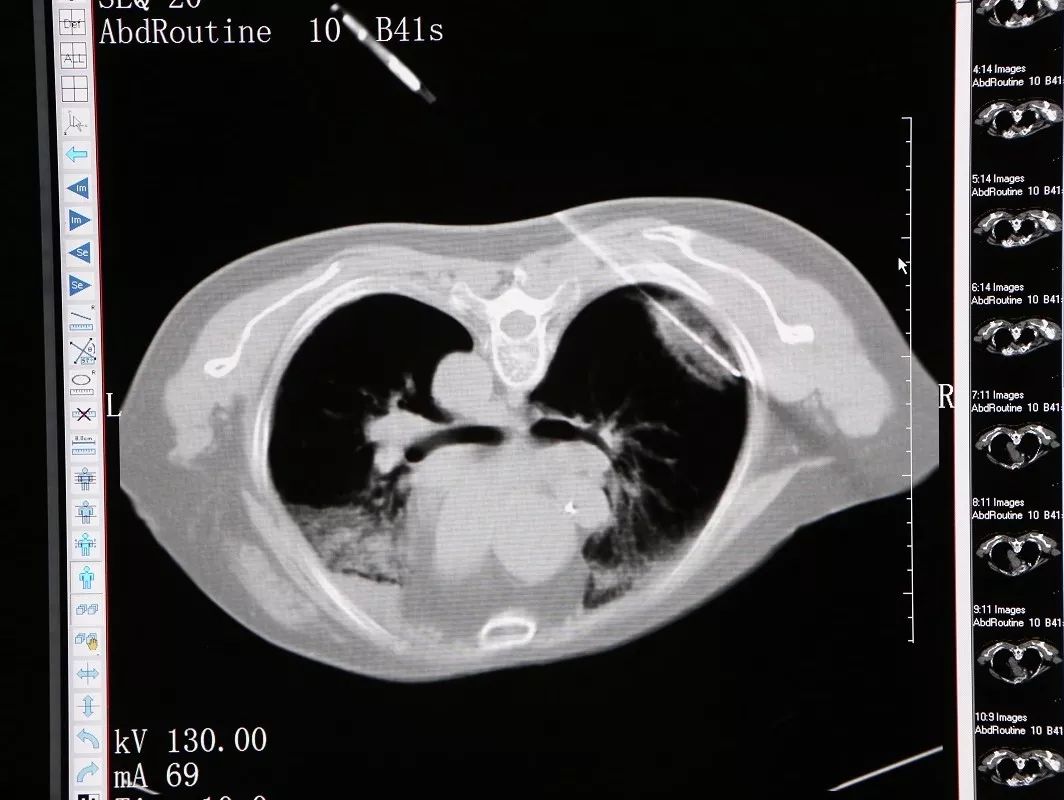

冷冻消融右肺背段结节

11月26日,穆阿姨被送至微创治疗室在CT引导静脉全麻下行右肺结节氩氦刀冷冻消融术,在实施静脉全麻后,术者将她摆成俯卧位,CT扫描以右肺背段近胸膜处结节为靶区,在CT引导下,用氩气超冷刀经穿刺点准确的穿刺到右肺结节,然后开始实施冷冻。术中通过CT扫描监测冷冻范围和有无并发症的发生,经过两个5分钟的冷冻循环后,CT扫描显示右肺的结节被成功的消融了。CT扫描见冰球覆盖靶区,复温后拔除超冷刀,包扎穿刺点,术中出血2ml,无手术标本,术后麻醉清醒,未诉不适,生命体征平稳。